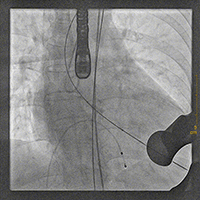

主动脉根部造影,确定瓣环位置

20mm球囊预扩张